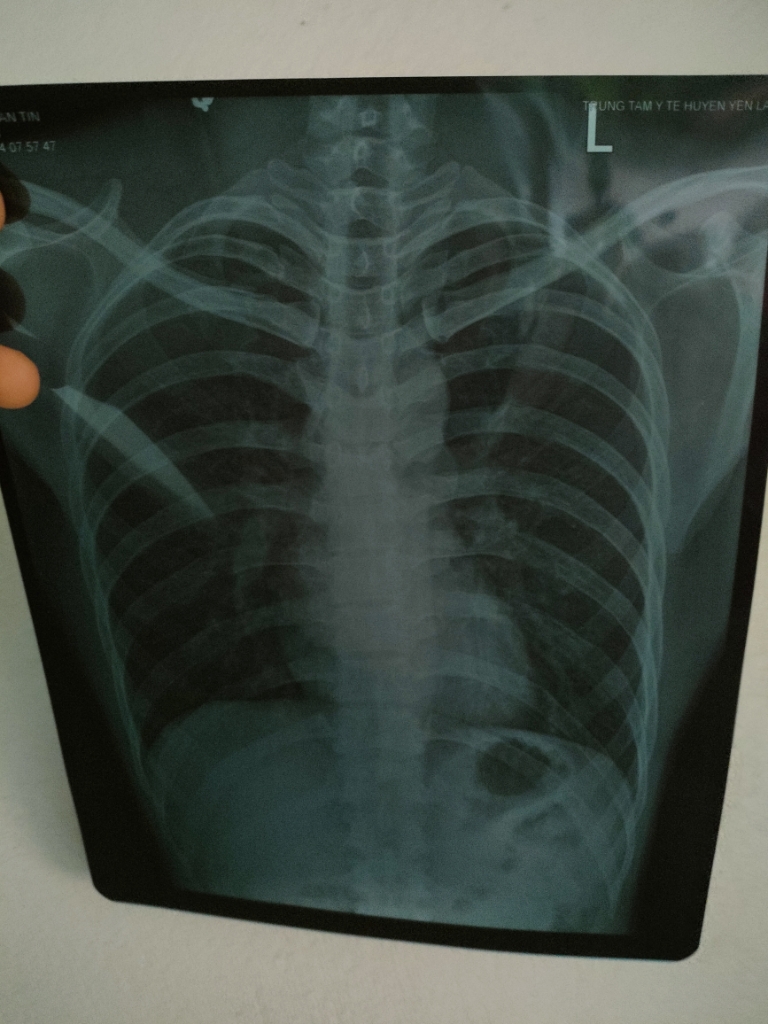

Dạ, đây là hình ảnh XQ của em ạ.